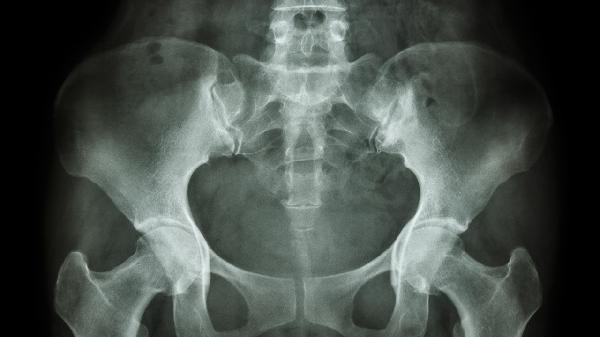

对乙酰氨基酚是孕期安全的镇痛药物,但需在医生指导下短期使用。局部可涂抹含有薄荷醇的外用药膏缓解肌肉紧张,禁止使用非甾体抗炎药。严重疼痛伴行走困难时,需排除耻骨联合分离超过10毫米的情况。